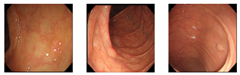

4. Experiments

Our dataset consisted of three types of images, which were used for training and testing our network. Sample images from our dataset can be seen in Figure 7, where Figure 7a shows colonoscopy images of a normal person, Figure 7b shows colonoscopy images containing an adenomatous polyp, and Figure 7c shows colonoscopy images containing a cancerous adenomatous polyp. As shown in Figure 7, the colon of a normal person is without any polyps in the mucosa. When a polyp develops in the colon of a normal person (see Figure 7b), it can develop into a relatively large adenomatous polyp (see Figure 7c). Adenocarcinoma of the adenomatous polyps develops into malignant tumors and become cancer. The shape and size of the polyps developed by the cancer appear in various forms without any specific rules (see Figure 7c).

Figure 7.

Endoscopy image type in this experiment. (a) Normal images; (b) adenoma images; (c) adenocarcinoma images.